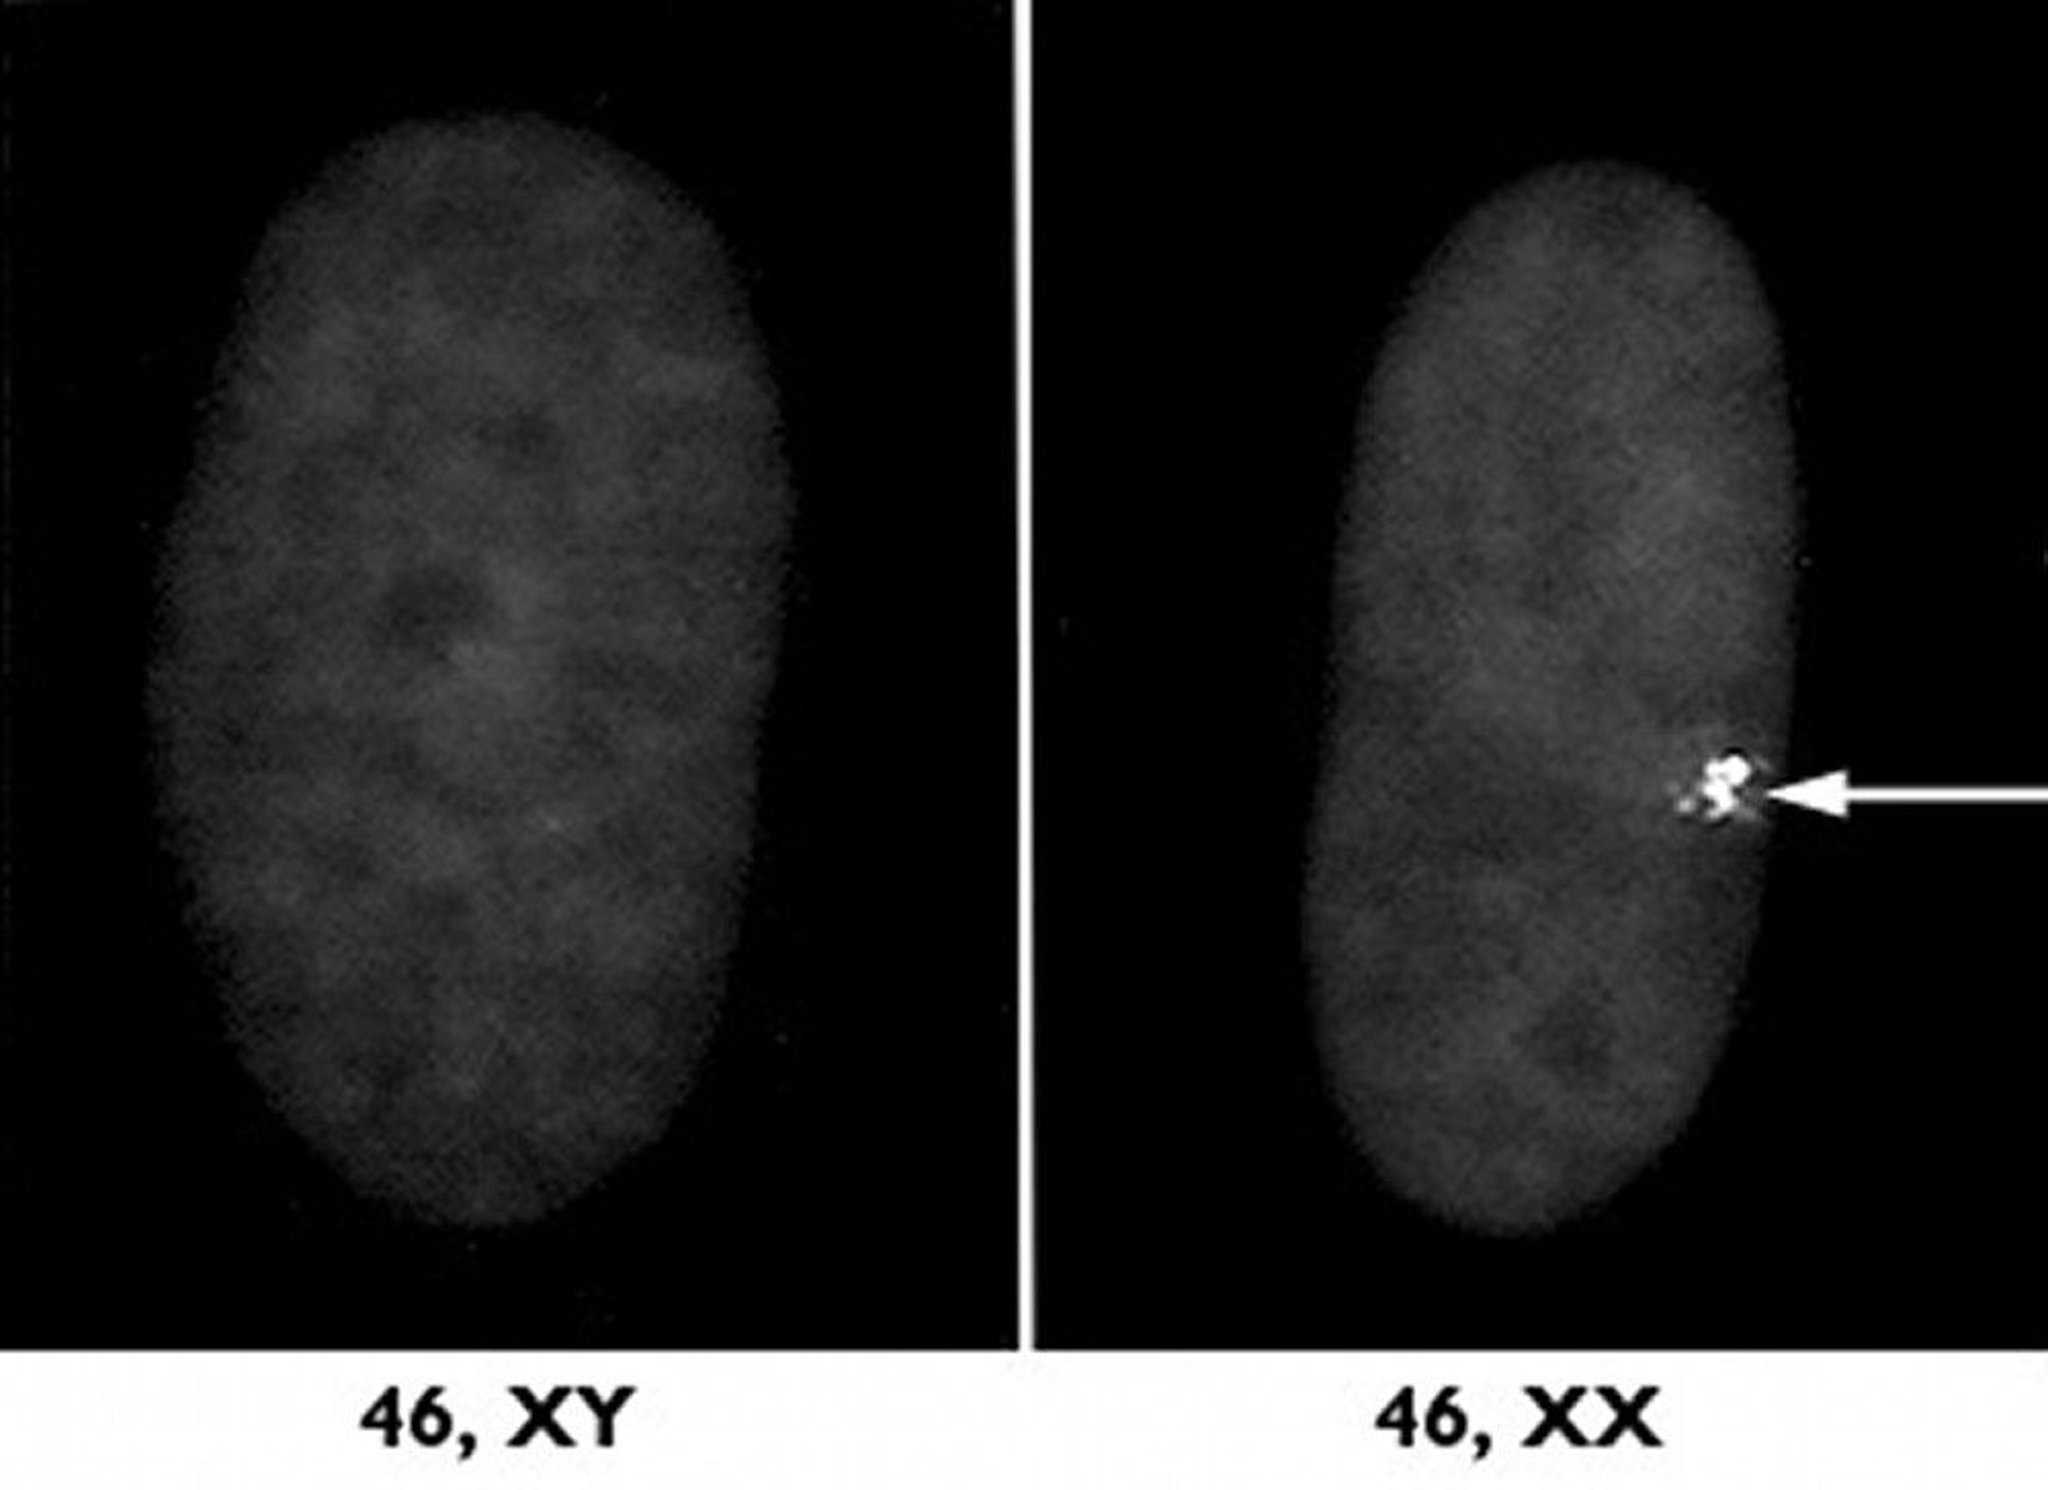

The pair of sex chromosomes determines whether a fetus becomes male or female. Males have one X and one Y chromosome. A male’s X comes from his mother and the Y comes from his father. Females have two X chromosomes, one from the mother and one from the father. In certain ways, sex chromosomes function differently than nonsex chromosomes.

The smaller Y chromosome carries the genes that determine male sex as well as a few other genes. The X chromosome contains many more genes than the Y chromosome, many of which have functions besides determining sex and have no counterpart on the Y chromosome. In males, because there is no second X chromosome, these extra genes on the X chromosome are not paired and virtually all of them are expressed. Genes on the X chromosome are referred to as sex-linked, or X-linked, genes.

Normally, in the nonsex chromosomes, the genes on both of the pairs of chromosomes are capable of being fully expressed. However, in females, most of the genes on one of the two X chromosomes are turned off through a process called X inactivation (except in the eggs in the ovaries). X inactivation occurs early in the life of the fetus. In some cells, the X from the father becomes inactive, and in other cells, the X from the mother becomes inactive. Thus, one cell may express a gene from the person’s mother and another cell expresses the gene from the person’s father. Because of X inactivation, the absence of one X chromosome usually results in relatively minor abnormalities (such as Turner syndrome). Thus, missing an X chromosome is far less harmful than missing a nonsex chromosome (see Overview of Sex Chromosome Abnormalities).